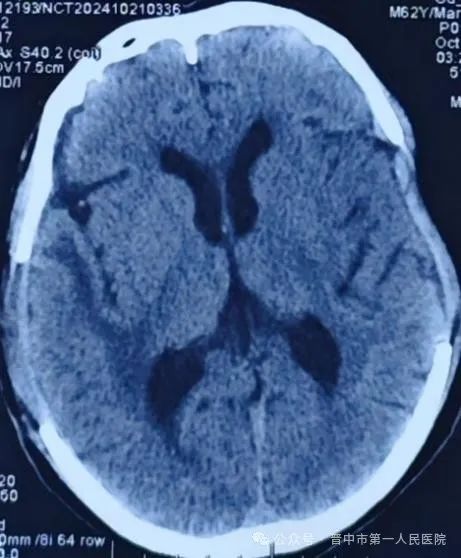

第一次术前:双侧颅内出血,出血量大

第一次术后:血肿完全清除